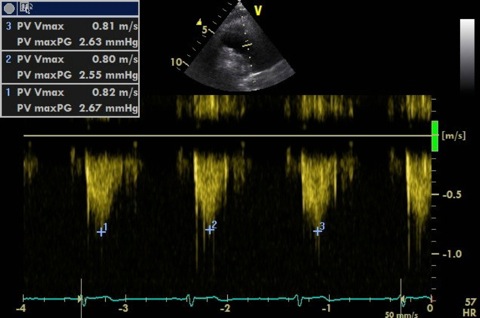

Doppler

CW

- Measure peak velocity of forward flow for stenosis and trace VTI for mean gradient (BSE recommends PW PV inflow for mean gradient).

- Align with regurgitant jet to measure peak velocity (used to calculate PADP). PR Vmax end diastole for end PADP and PR Vmax early diastole for mean PADP.